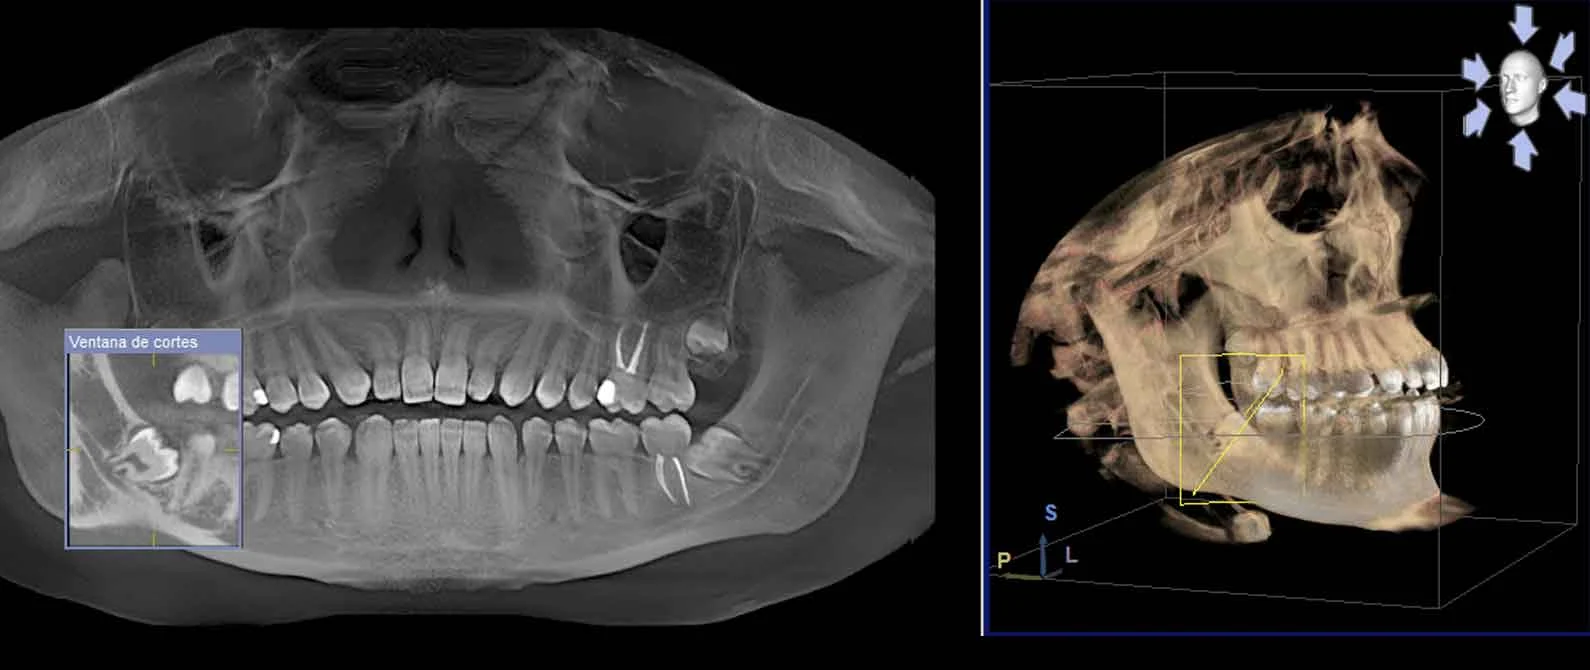

Che cos’è la TAC Cone Beam?

- Definizione di CBCT (Cone Beam Computed Tomography): tecnologia radiologica 3D che utilizza un fascio di raggi X a forma di cono per acquisire l’intero volume da indagare in un’unica rotazione.

- Funzione di acquisizione volumetrica 3D con un solo sensore digitale: il tomografo Cone Beam effettua una scansione completa in pochi secondi, raccogliendo dati multidirezionali che vengono poi elaborati da software dedicati.

- Rapporto 1:1 tra immagini e anatomia, senza bisogno di mezzo di contrasto: ogni voxel acquisito corrisponde esattamente a una porzione anatomica reale, garantendo misurazioni precise di altezza e spessore osseo per implantologia e pianificazione chirurgica.

La TAC Cone Beam (o CBCT) si distingue dalla TAC tradizionale perché sfrutta un unico sensore digitale che ruota attorno al paziente, evitando numerose rotazioni multiple e riducendo così la dose di radiazioni. Grazie alla scansione conico-fascio, è possibile ottenere una visione volumetrica del cranio, delle arcate dentali (superiore e inferiore) e del massiccio facciale, utile per:

La formidabile precisione della CBCT deriva dal rapporto 1:1 tra voxel e anatomia, che permette di:

- Produrre ricostruzioni multiplanari (MPR) nei piani assiale, sagittale e coronale